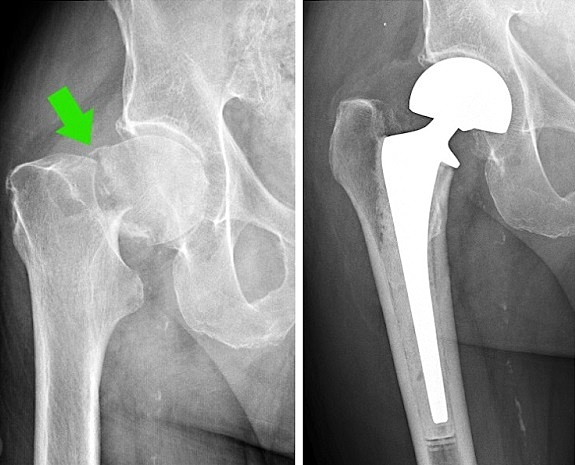

O SAMU 192 foi acionado e, durante a imobilização do paciente, percebeu que o mesmo fraturou a cabeça do fêmur. Caracterize, anatomicamente, a articulação lesada (ligamentos e cápsula).

_______________________________________________________________________________________________________________________________________________________________________________________________________________________________ (Fonte da imagem: http://www.medicinanet.com.br/conteudos/casos/7677/fratura_de_femur.htm)